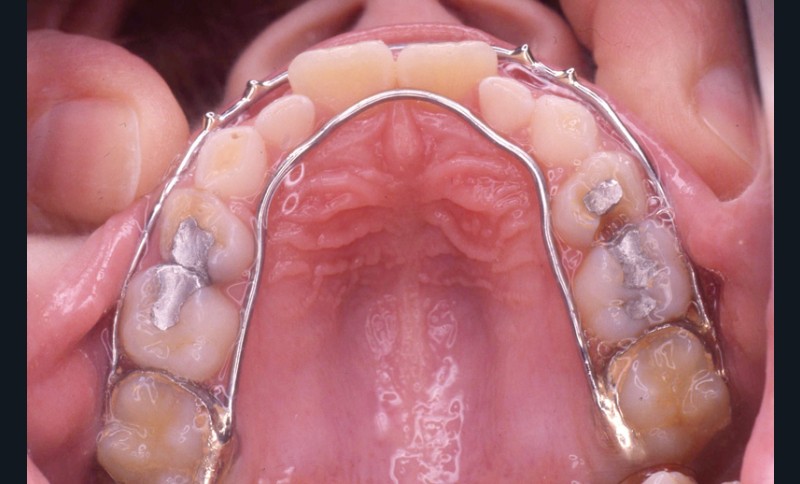

L’examen de la denture (fig. 3 à 5) montre :

• dans le sens antéro-postérieur, des relations molaires et canines de type classe III d’Angle et une inversion des rapports incisifs,

• dans le sens transversal, une endomaxillie bilatérale prédominante dans la région canine.